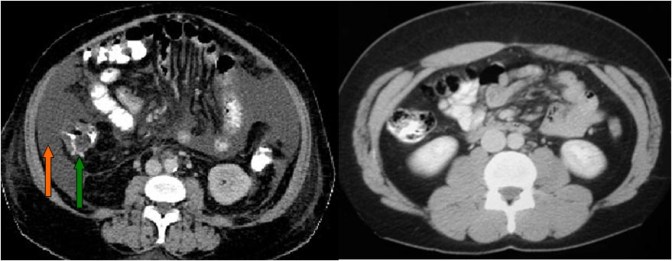

Normalmente en la radiografía simple de abdomen vemos una banda vertical poco densa (grasa del flanco) entre el colon ascendente o descendente y la pared abdominal. Cuando existe hemoperitoneo o ascitis, el líquido se introduce en este espacio, ensanchándolo y oscureciendo las haustras del colon y la línea peritoneal. En la imagen ampliada vemos la banda grasa del flanco estrechada y un aumento de la distancia desde esta línea hasta el colon.

Radiografía de abdomen normal que muestra las líneas grasas de los flancos (flechas).

A la izquierda, corte de TC de abdomen con contraste oral e intravenoso que muestra abundante líquido ascítico, especialmente acumulado en los flancos. Obsérvese como el líquido (flecha naranja) desplaza medialmente el colon (flecha verde). A la derecha, un estudio normal para comparar.